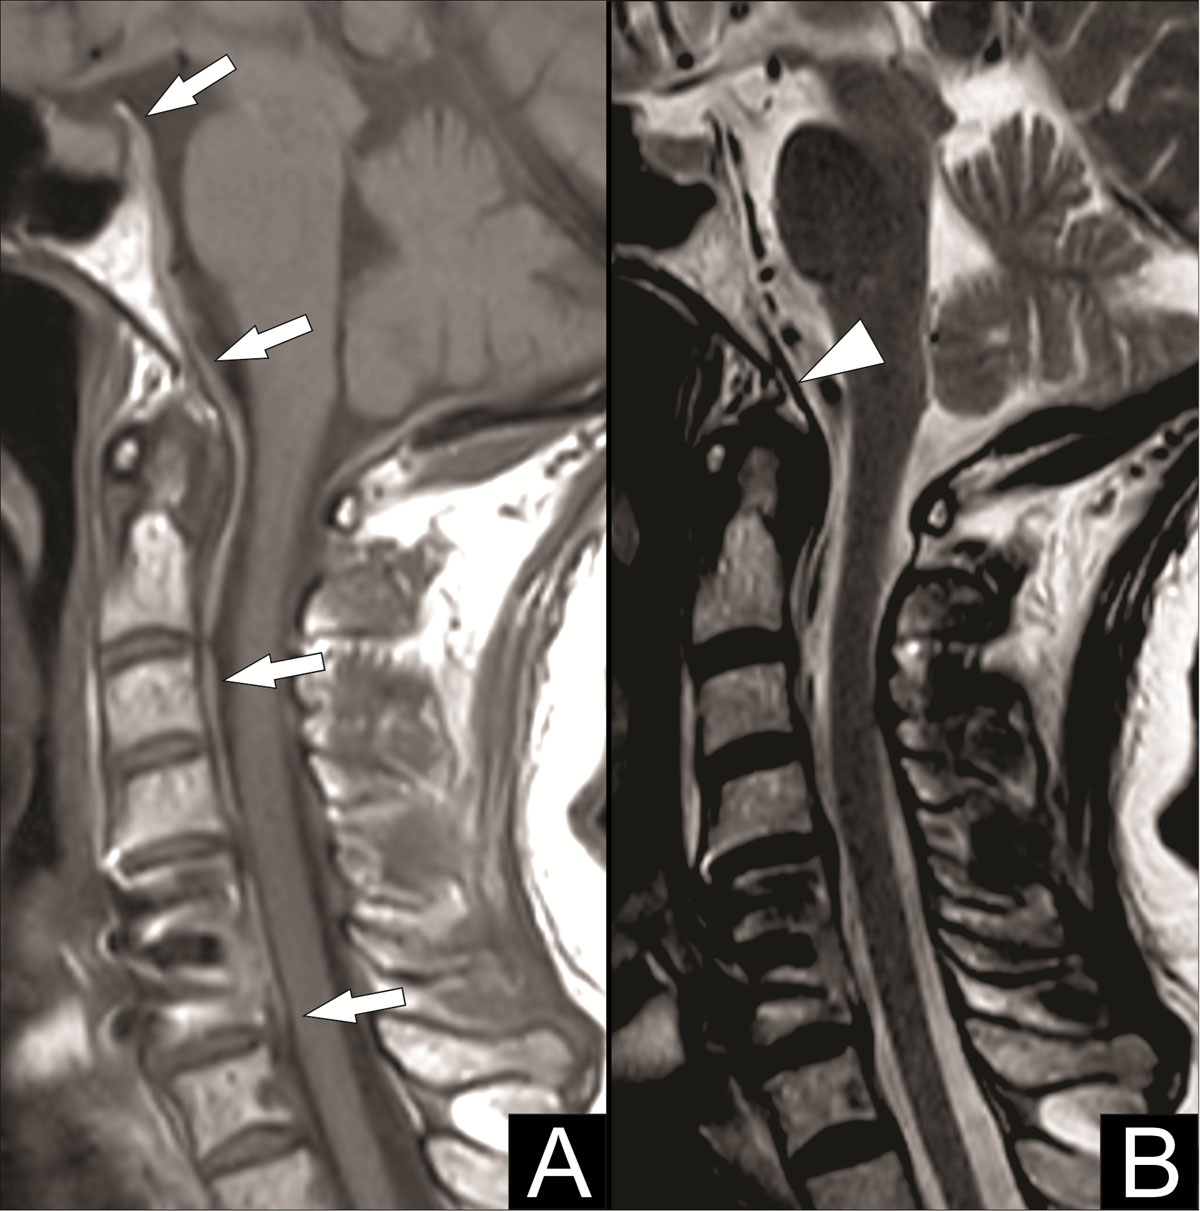

Magnetic resonance imaging (MRI) of the cervical spine was then performed to assess this collection better. MRI showed a hematoma posterior to the tectorial membrane descending anteriorly into the spinal canal up to the posterior body of C6, best seen on T1-weighted images (Figure 3A, white arrows), and an intact tectorial membrane, best seen on T2-weighted images (Figure 3B, white arrowhead). These imaging findings are suggestive of a retroclival subdural hematoma.

Figure 3

The tectorial membrane is vital in distinguishing between a subdural and an epidural retroclival hematoma. The tectorial membrane extends from the posterior longitudinal ligament and attaches to the posterior body of C2 and the clivus. Because of a tight adherence of the spinal dura to the tectorial membrane at the C2 level, epidural retroclival hematomas cannot descend below this C2 level. Subdural hematomas, on the other hand, are not restricted by the tectorial membrane and can descend below the C2 level into the spinal subdural space. Furthermore, the tectorial membrane is often ruptured with an epidural hematoma and remains intact with a subdural hematoma [1].